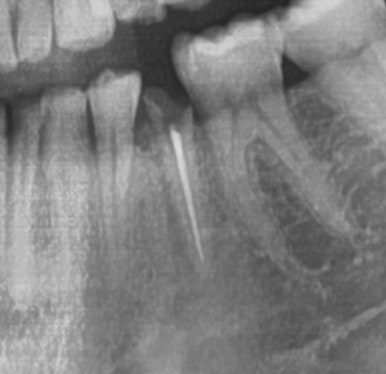

신경치료하고 크라운 안 한 치아->파절

위의 케이스도 비슷합니다.

신경치료를 외국에서 했는데 외국에서는 크라운 비용이 더 비싸다보니 방치해서

크라운으로 치아를 감싸지 못해 치아가 다 부러지고 저렇게 뿌리부분만 남아

크라운조차 할 수 없는 경우가 많습니다.